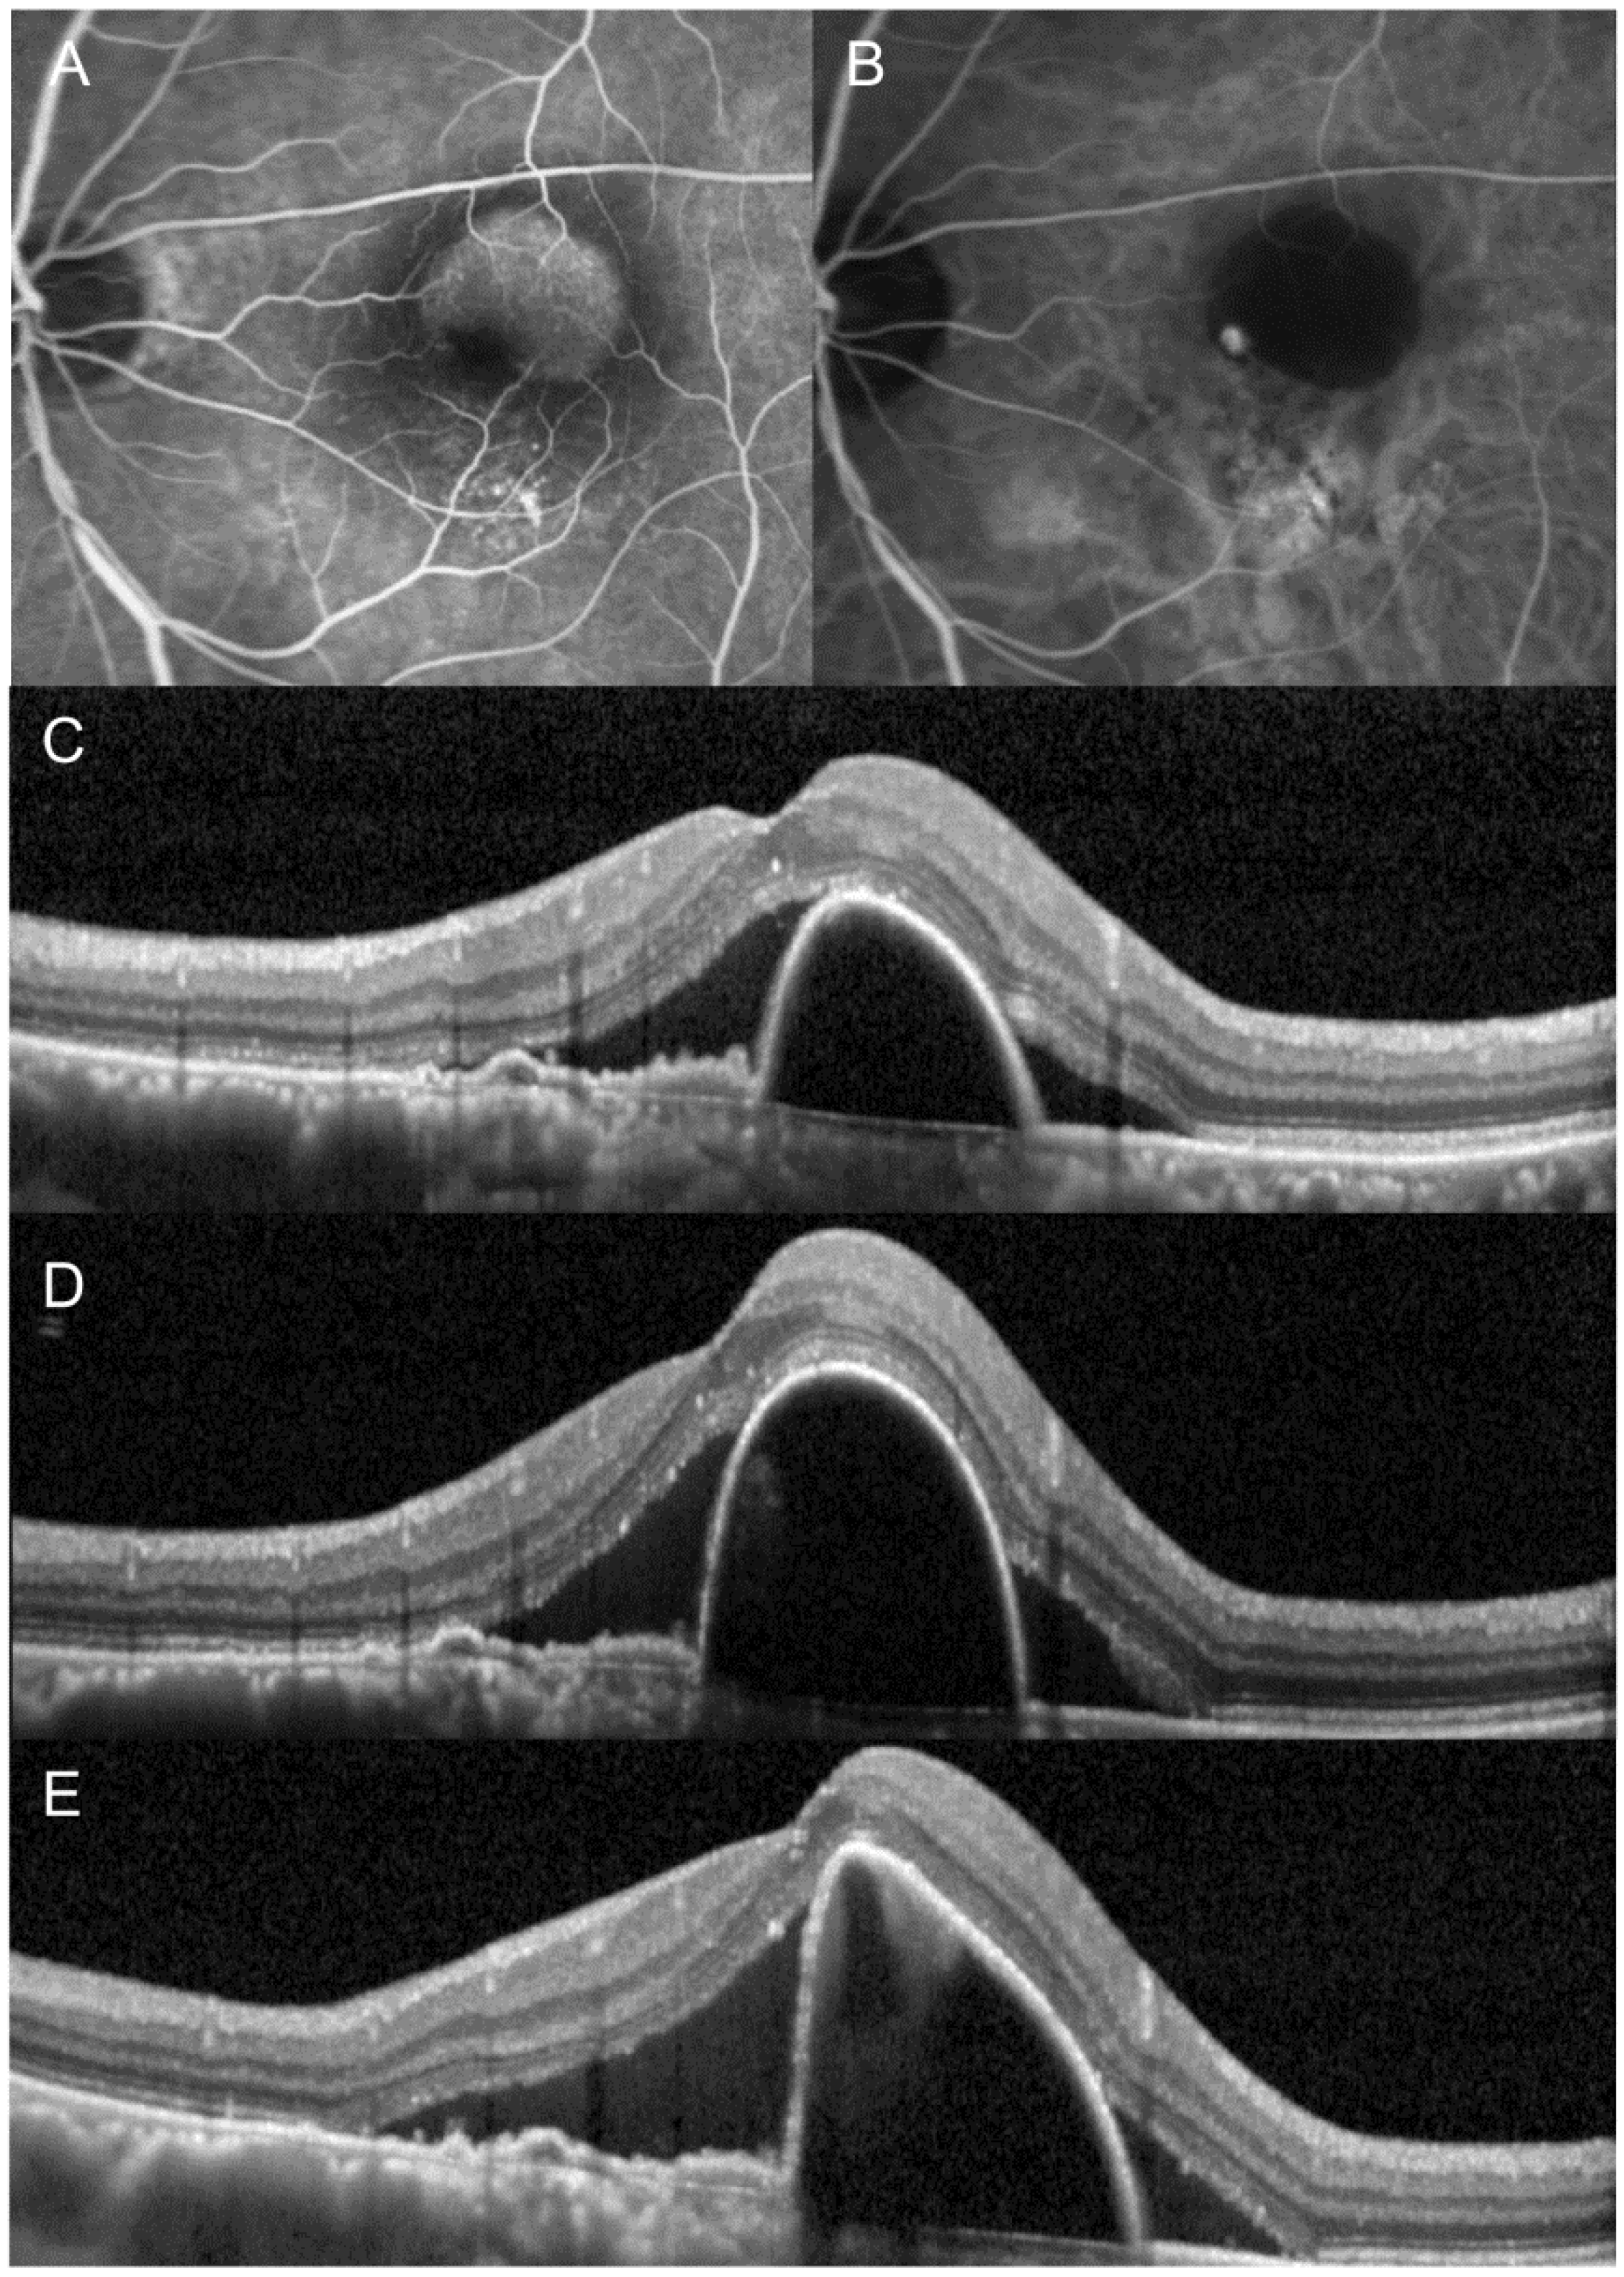

3. Results